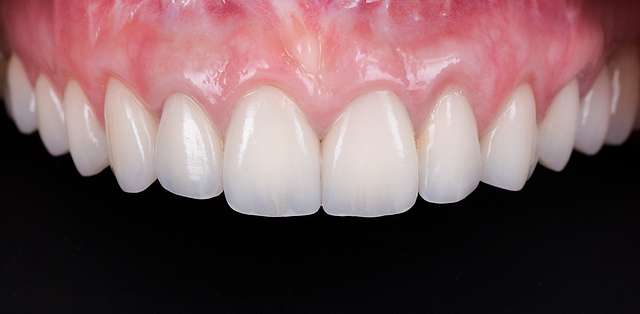

Grefe pentru corectia nivelului si a retractiei gingivale

Fiecare caz este planificat digital, si este executat cu cea mai potrivita procedura. Rationamentul folosit pentru selectia celei mai potrivite proceduri, consta in raportul dintre cel mai longeviv rezultat si cea mai putin invaziva procedura. Chirurgia ghidata

Focusul este pe cel mai bun rezultat final, atat din punct de vedere estetic cat si durabil. In cazurile complexe cu indicatii deosebite, Dentcof dispune si de logistica necesara colaborarii cu specialisti internationali. Vezi echipa